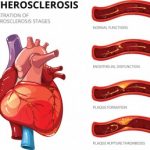

Systemic sclerosis (scleroderma) is an independent risk factor for atherosclerosis

Systemic sclerosis (scleroderma) is an independent risk factor for atherosclerosis

Systemic sclerosis – scleroderma – is an independent risk factor for atherosclerosis, which is hardening of the arteries. The findings come from researchers in Hong Kong who uncovered that scleroderma can contribute to atherosclerosis. Among the known risk factors for atherosclerosis are age and hypertension.

Scleroderma is a connective tissue disorder in which the tissue of the skin becomes hardened due to an increase in collagen. It is estimated that 49,000 Americans suffer from scleroderma. Research has revealed that scleroderma patients are often at a higher risk for coronary artery disease, the risk factors for which has long been unknown.

The research team, led by Dr. Mo Yin Mok, recruited 53 scleroderma patients and 106 healthy controls to examine coronary artery calcium scores and cardiovascular risk factors. Disease activity score, antiphospholipid antibodies, C-reactive protein, and erythrocyte sedimentation rate were also measured among scleroderma patients.

Upon analysis completion, researchers found that 57 percent of scleroderma patients had moderate to severe coronary calcification, compared to only 29 percent of the healthy controls. Scleroderma patients also had lower LDL cholesterol, HDL cholesterol, and diastolic blood pressure, compared to the controls. Furthermore, one-third of the group also had low body mass index compared to the controls, many of them being considered underweight among the Asian population.

Lastly, systemic sclerosis was found to be an independent risk factor for atherosclerosis. The longer a person has had scleroderma, the worse their atherosclerosis was.

Dr. Mok concluded, “Our findings show that systemic sclerosis patients have an 11-fold increased risk for developing moderate to severe coronary calcification after adjustment for normal cardiovascular risk factors. CAD is a major global health concern, and further studies should explore modifiable disease-specific risk factors in scleroderma patients that could inhibit coronary calcification in this population.” Continue reading…